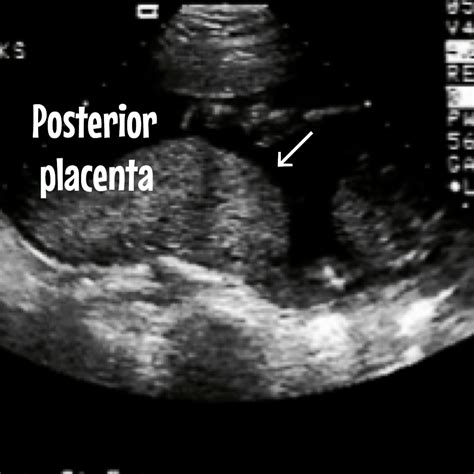

The placenta is a vital organ that develops in the uterus during pregnancy. It provides oxygen and nutrients to the growing fetus and removes waste products from the baby's blood. The position of the placenta can vary, and one of the common positions is the posterior position. When the placenta is described as posterior, it means that it is attached to the back wall of the uterus. This position is relatively common and is often discovered during routine ultrasound examinations.

• Posterior Placenta: Attached to the back wall of the uterus.